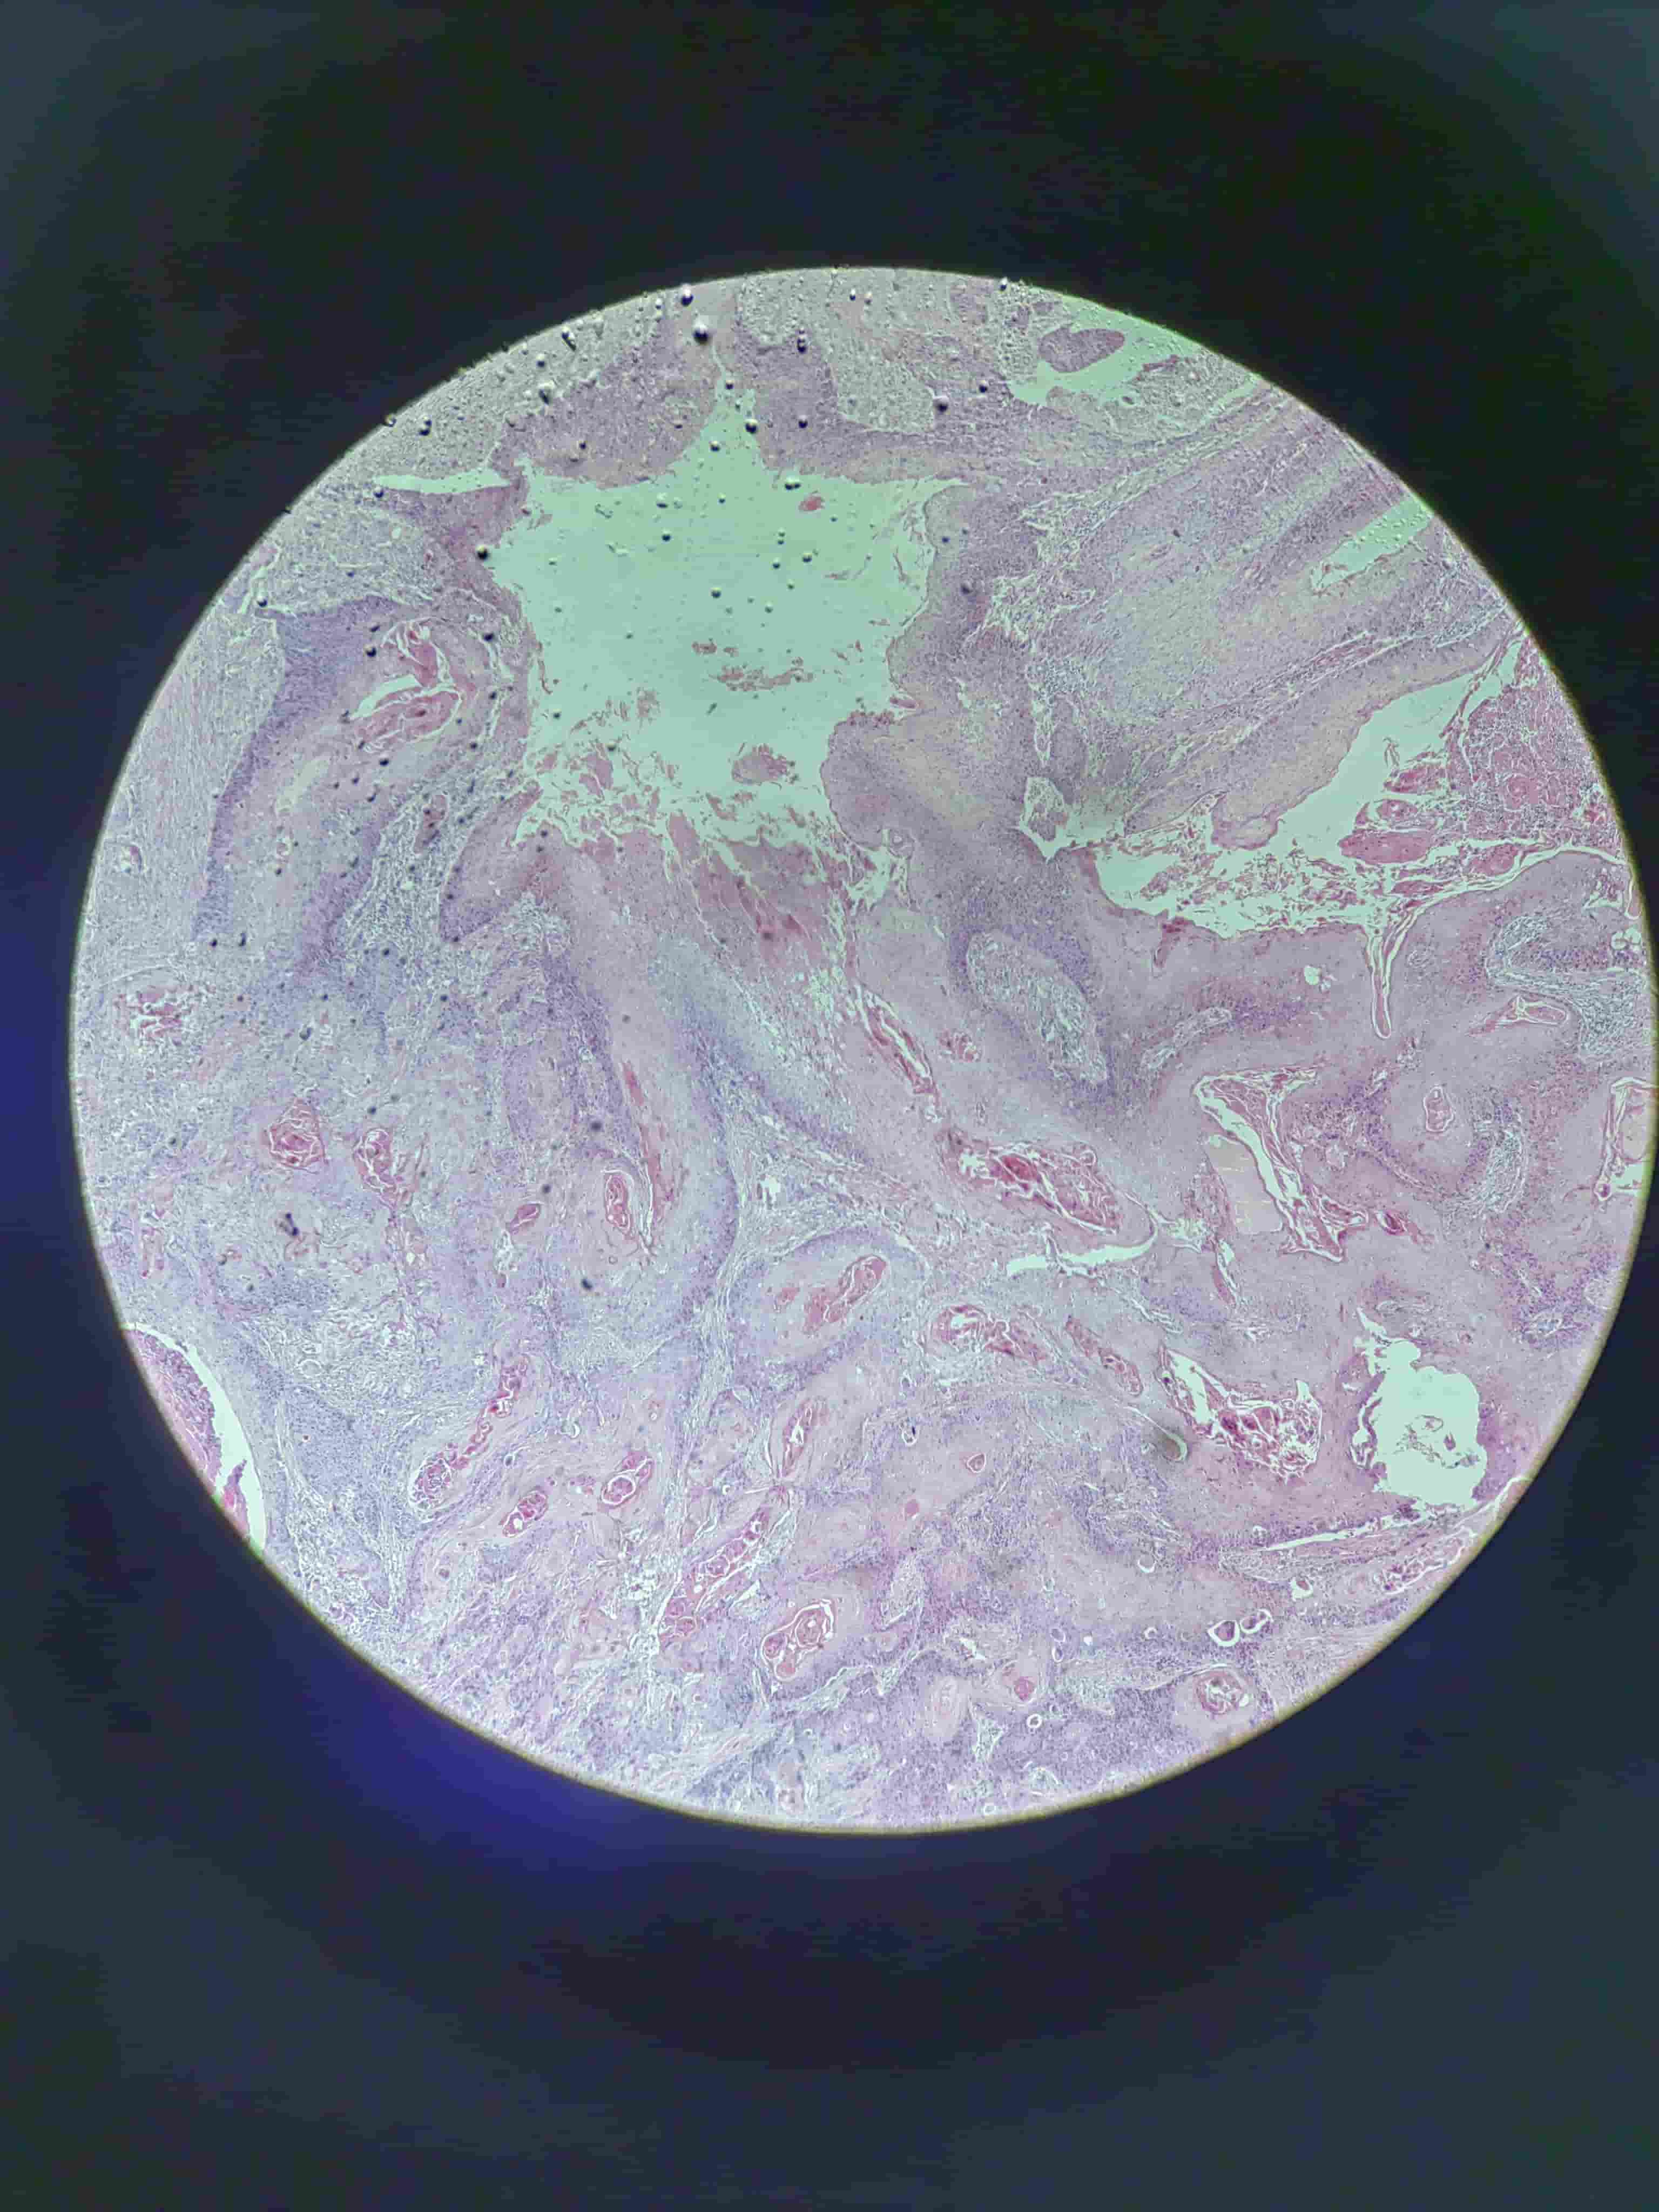

鳞状细胞癌